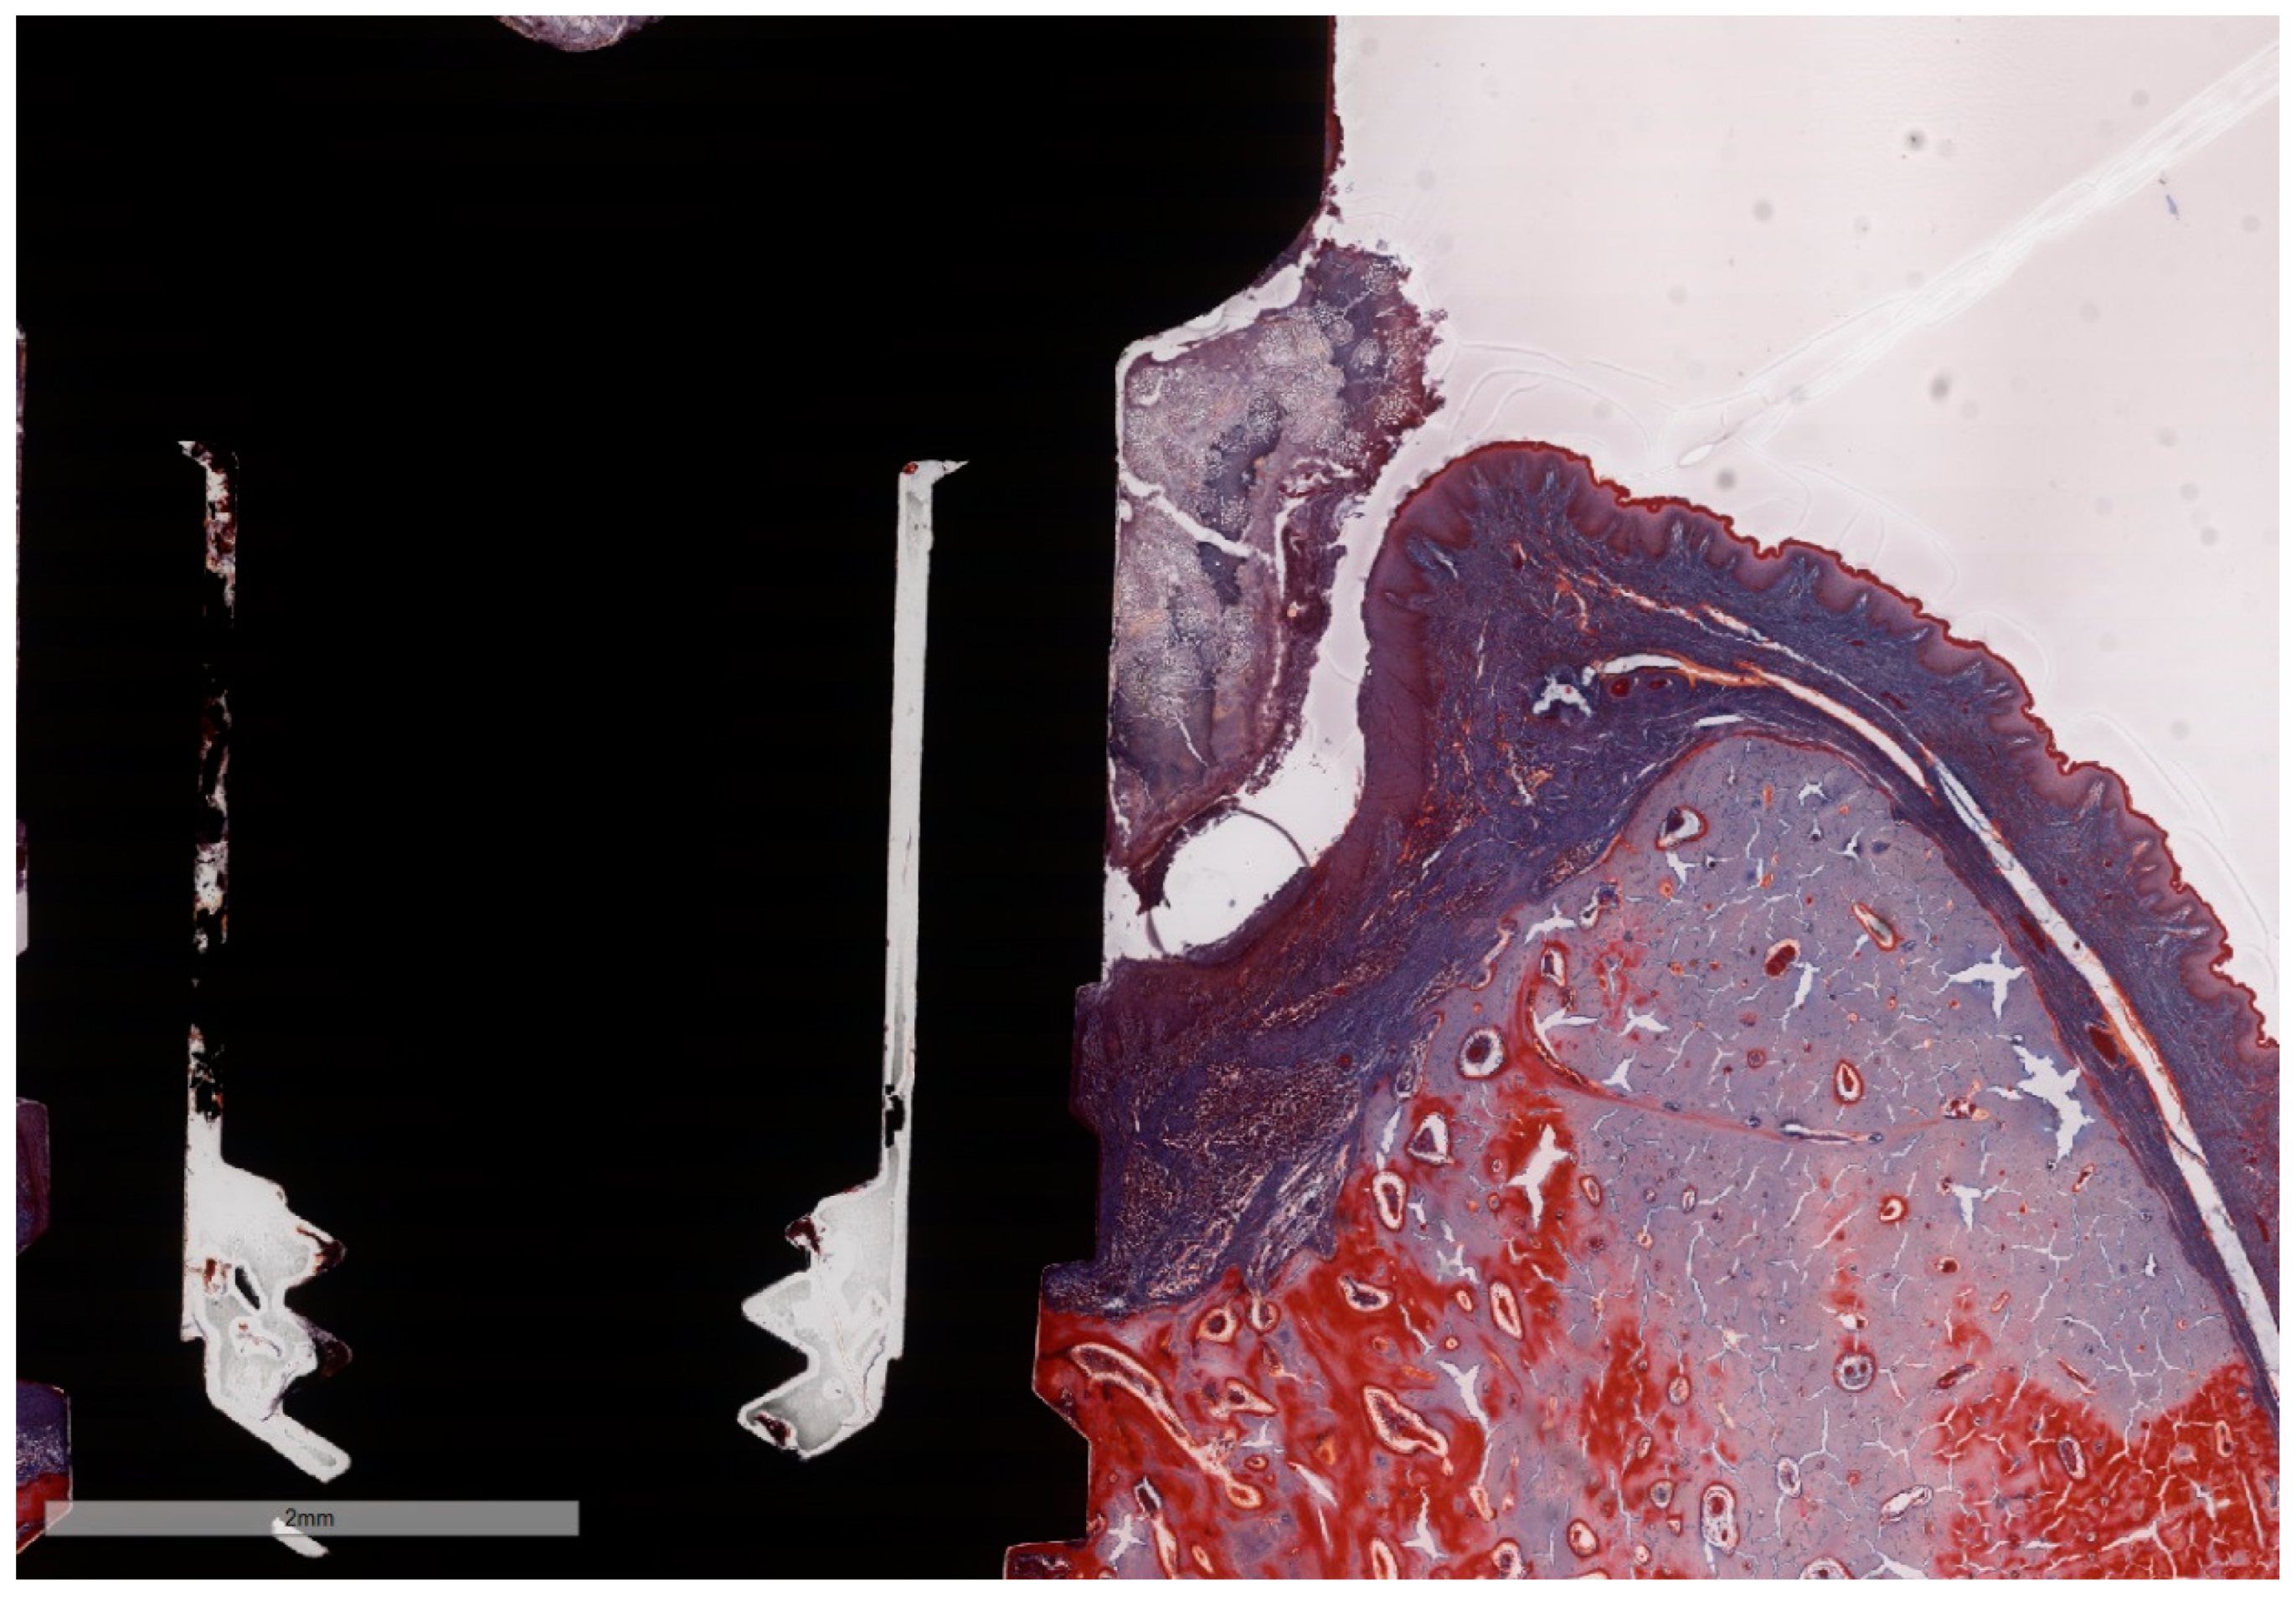

Figure 7. Histomorphometric landmarks identified on both buccal and lingual aspects in each implant: 1—implant shoulder (IS); 2—implant surface at the level of the bone crest (imp); 3—bone crest, defined as the most coronal point of the bone (BC); 4—bottom of the bone defect (BD); 5—margin of the peri-implant mucosa (PM); 6—the apical termination of the junctional epithelium (aJE); 7—the coronal level of the infiltrated connective tissue (cICT); 8—the apical extension of the infiltrated connective tissue (aICT); 9—the most apical extension of the submarginal biofilm that was interposed between the implant and the pocket epithelium of the peri-implant mucosa (aPlaque). (Implant #5, mirroring sections, (A)—Masson Goldner Anilin blue stain, (B)—Movat Pentachrome stain, original magnification ×2).

3.2. Histometric Findings

Due to the particularities of the MGA and MOV stainings, some measurements succeeded better on MGA than on MOV sections (Figure 7A,B). Moreover, artifacts resulting from the cutting–grinding process necessitated the complementing of measurements on both stainings in order to obtain values as accurate as possible.